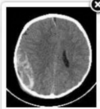

12

Q

An 8-month-old girl with developmental delay presents to the emergency department with new onset seizure activity. On exam, the patient has slightly reduced

muscular tone in the left upper and lower extremities. A non-contrast MRI is obtained (figure). What is the most likely diagnosis?

O Arachnoid cyst

O Lissencephaly

O Schizencephaly

O Porencephalic cyst

O Holoprosencephaly

A

Schizencephaly